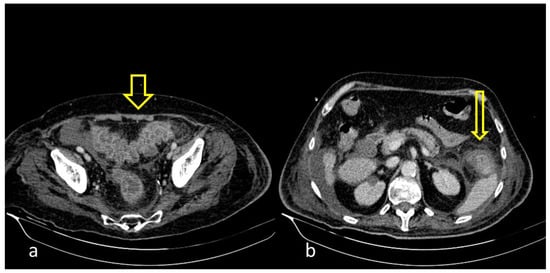

Figure 1. COVID-19 (+) hospitalized 75-year-old male patient with abdominal pain and diarrhea. Abdominal Contrast Enhanced CT (CECT) depicted bowel wall thickening ((a), thick arrow) and mesenteric fat stranding ((b), thin arrow). The imaging findings are indicative of inflammatory colitis.

A large bowel infection usually appears with diffuse circumferential and enhancing wall thickening (hyperenhancement) that can involve one or more segments of the colon (Figure 1 and Figure 2). Pericolic fluid or perintestinal fat stranding is common while pericolic lymphadenopathy is not (Figure 3 and Figure 4). If we suspect COVID-19-related colitis, clinical correlation is needed, and the detection of the virus in stools can establish the diagnosis.